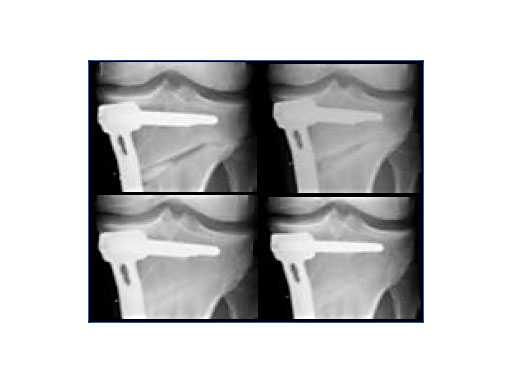

New implant developments are all based on comprehensive in-vitro and in-vivo investigations [2]. In open-wedge high tibial osteotomies, chronOS wedges are well suited for bridging, filling, and correcting bone defects when associated with a stable fixation system [3]. It has been observed that after twelve months various amounts of chronOS were completely resorbed and replaced by new bone (Fig.2).